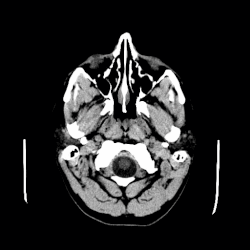

A CT scan of an arachnoid cyst

CT scan of a colloid cyst

The diagnostic process typically begins with a medical history workup followed by a medical examination by a physician. Imaging tests, such as CT scans and MRIs, help provide a clearer picture. The physician typically looks for fluid (or other bodily substance) filled sacs to appear in the scans, as is shown in the CT scan of a colloid cyst. A primary health care provider will refer an individual to a neurologist or neurosurgeon for further examination. Other diagnostic methods include radiological examinations and macroscopic examinations. After a diagnosis has been made, immunohistochemistry may be used to differentiate between epithelial cysts and arachnoid cysts.[2] These examinations are useful to get a general idea of possible treatment options, but can be unsatisfactory to diagnose CNS cysts.[3][5] Professionals still do not fully understand how cysts form; however, analyzing the walls of different cyst types, using electron microscopes and light microscopes, has proven to be the best diagnostic tool. This has led to more accurate cyst classification and correct course of action for treatments that are cyst specific. In the past, before imaging scans or tests were available, medical professionals could only diagnose cysts via exploratory surgery.[2]